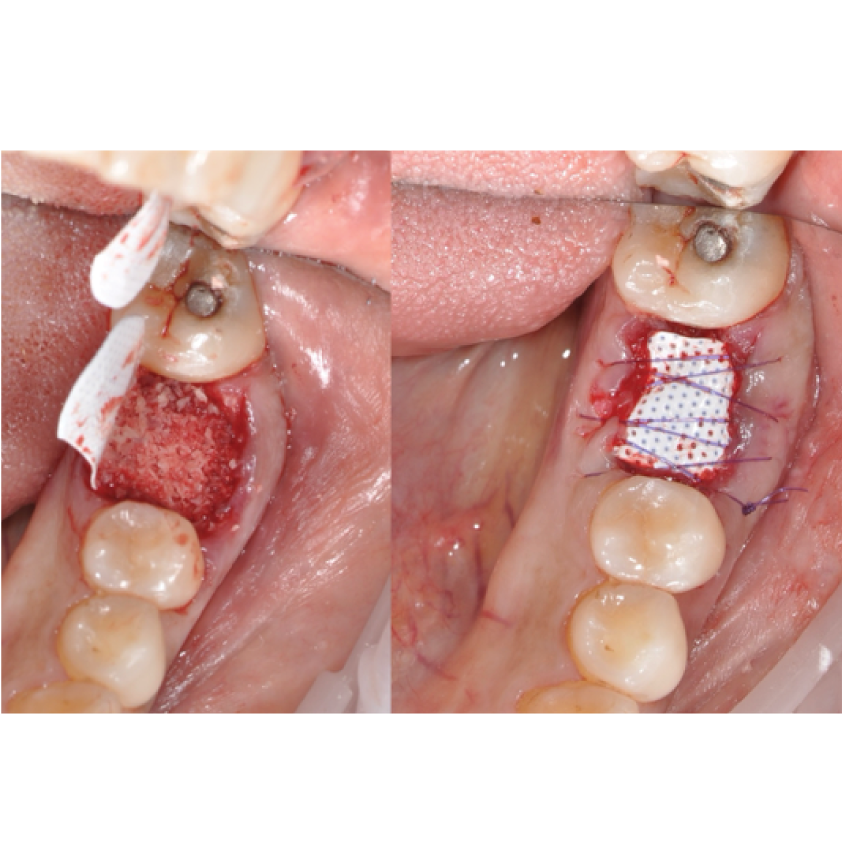

Director’s Clinical Cases

Director’s Clinical Cases